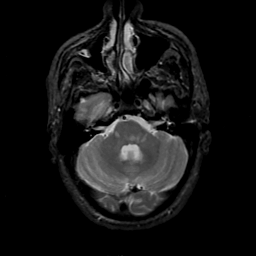

MR Study #18, July 21, 1991 -- Slice #12